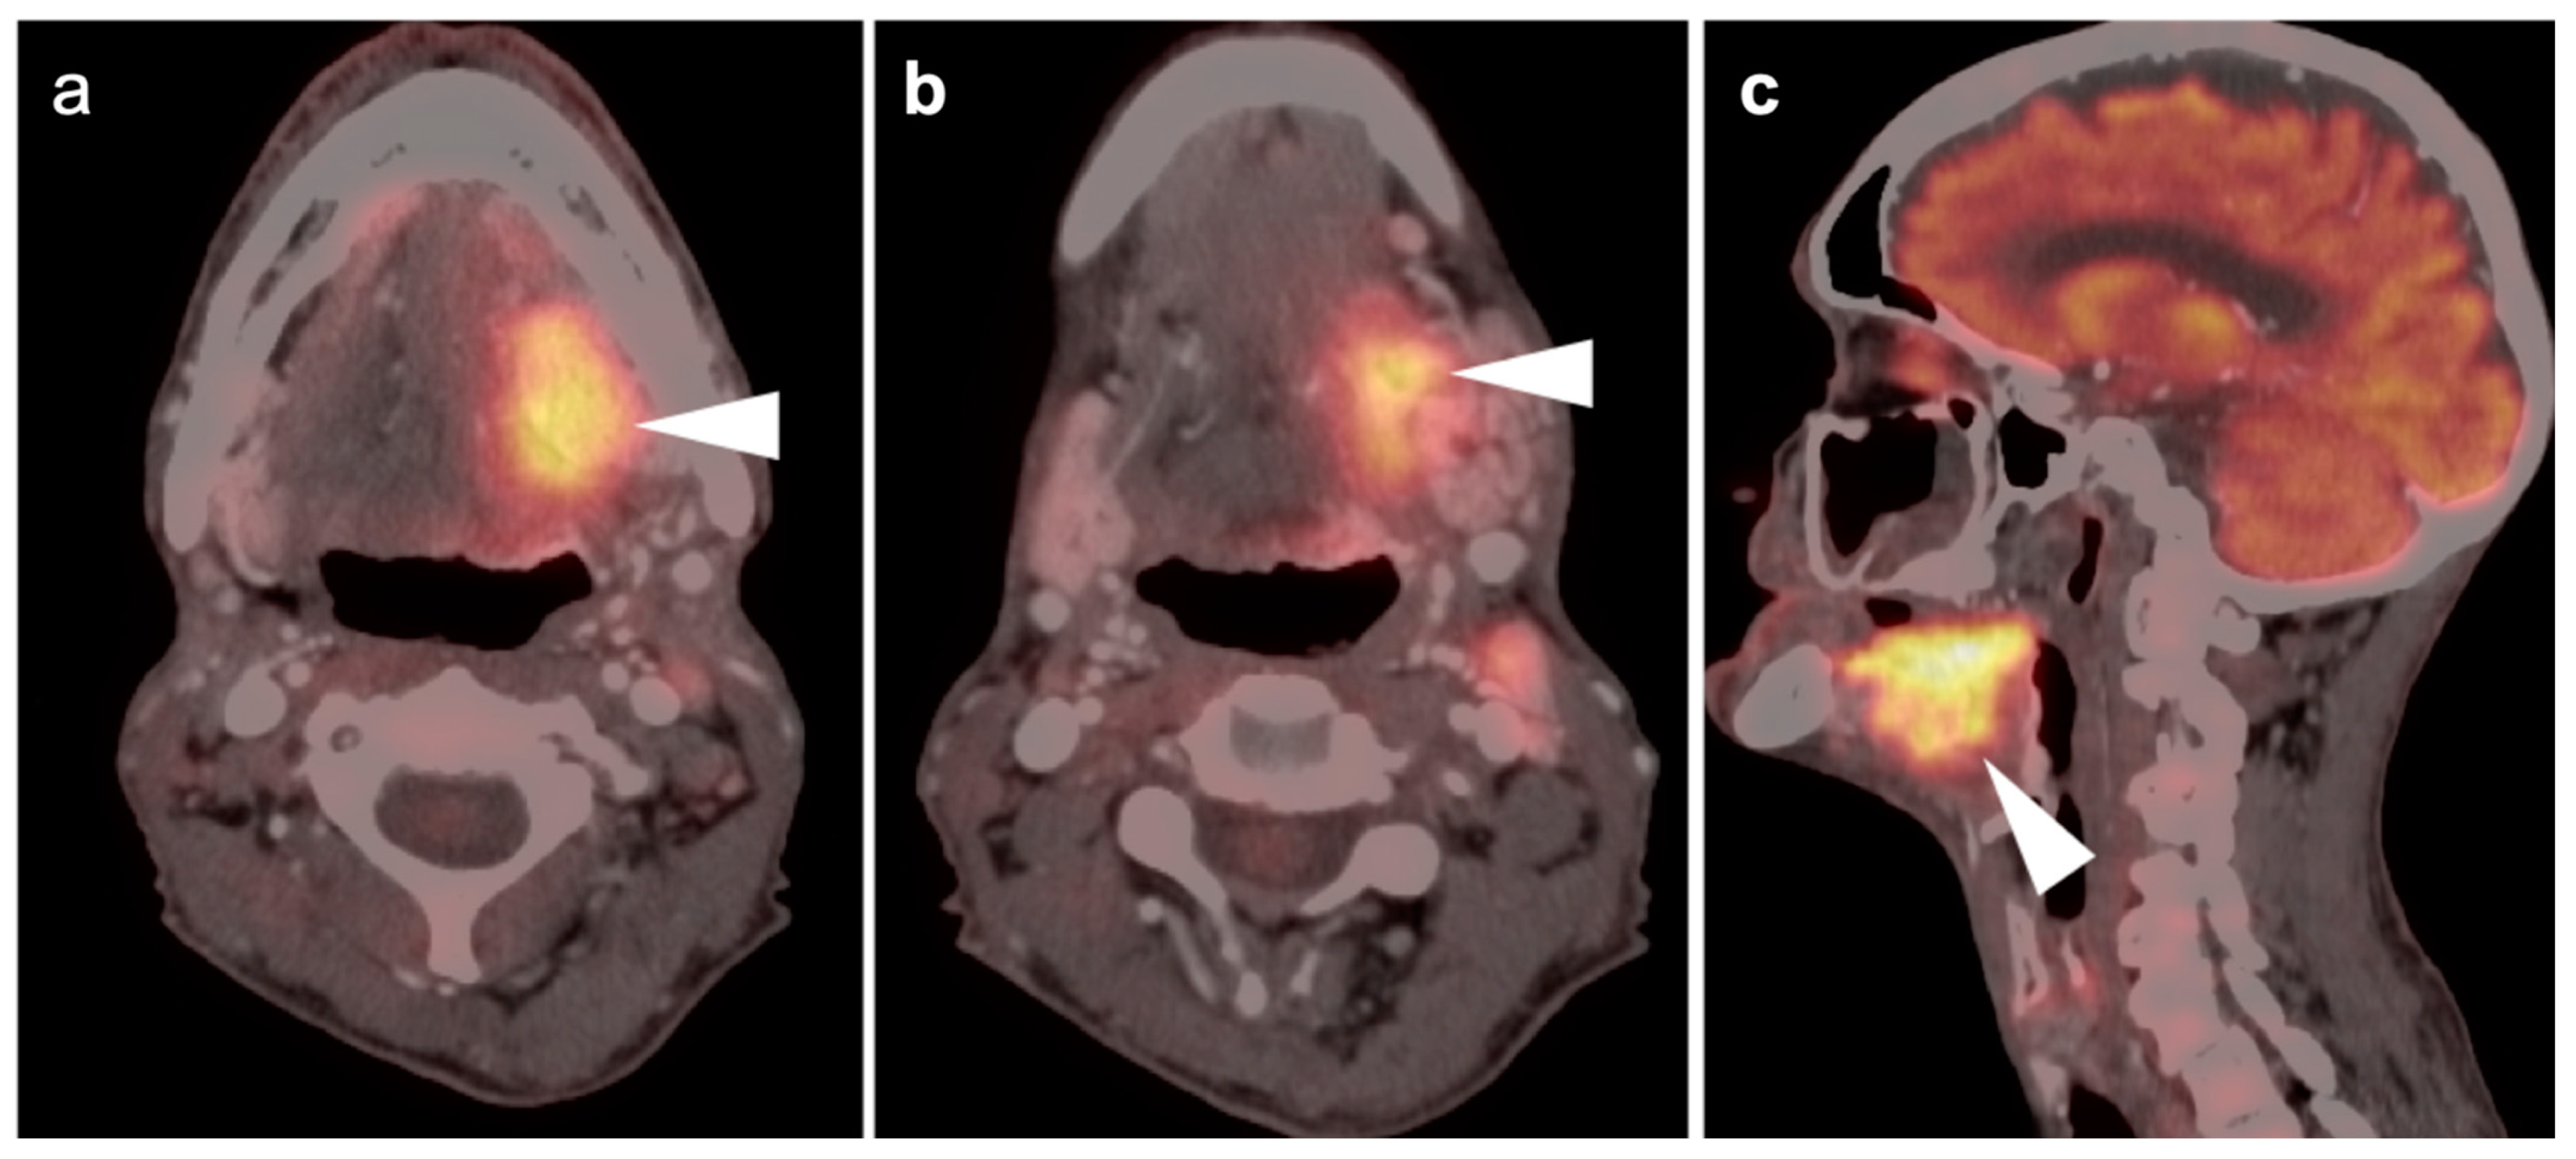

2.6. Thyroid Cancer

- Differentiated thyroid cancer

- Anaplastic thyroid cancer